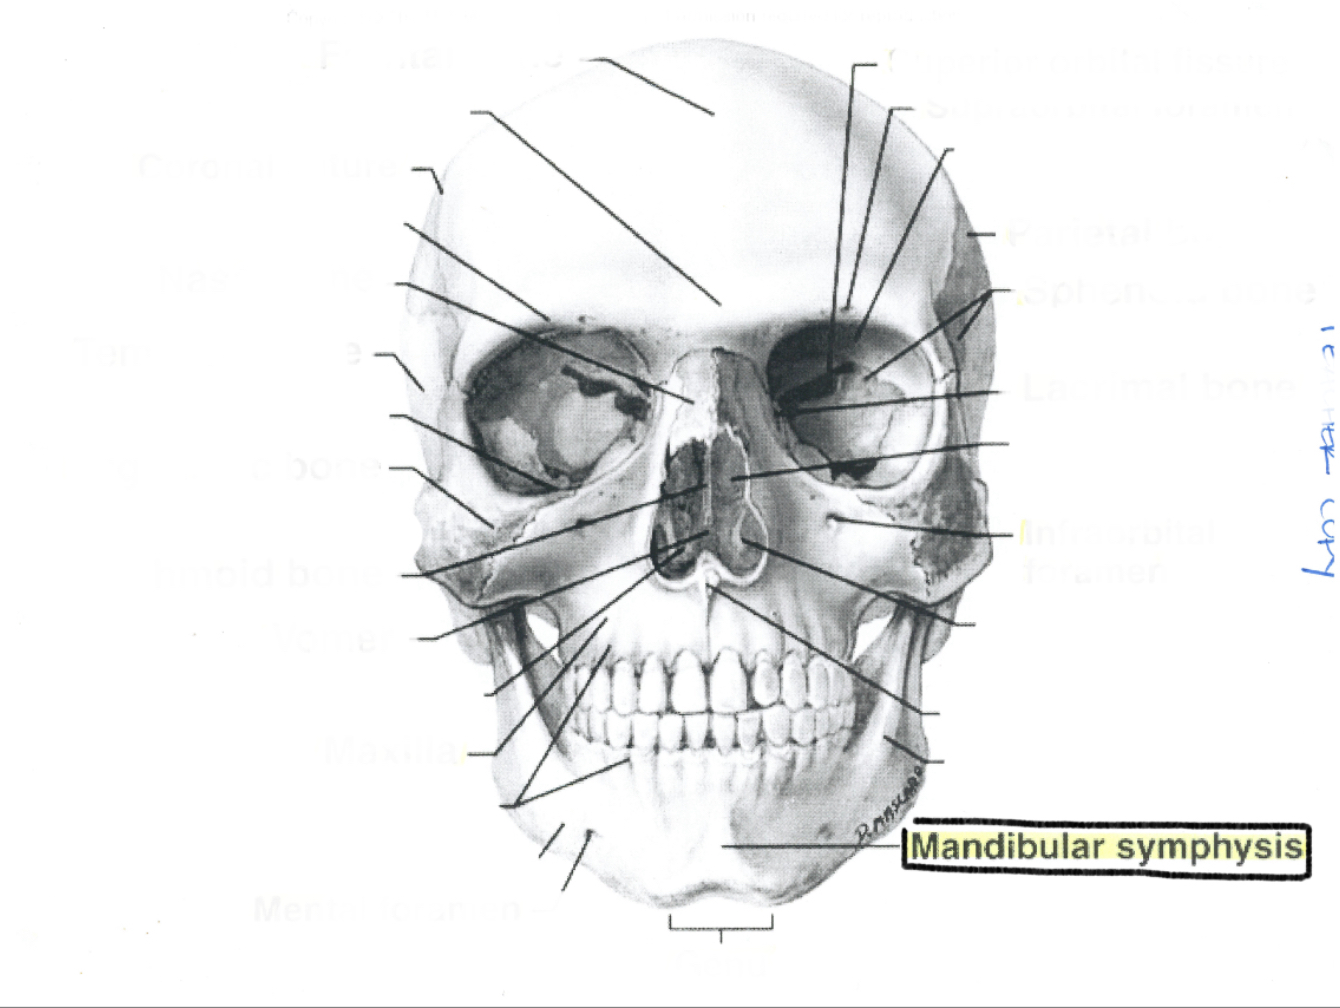

Mandibular symphysis